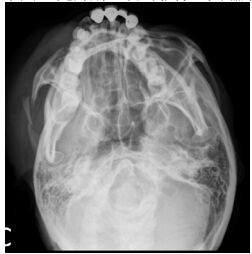

77.下圖 X 光片所呈現的放射線透性(radiolucent)影像,其臨床診斷最可能為下列何者?(A) 鱗狀細胞癌(squamous cell carcinoma) (B) 囊腫(cyst) (C) 肉芽腫(granuloma) (D) 骨瘤(osteoma)